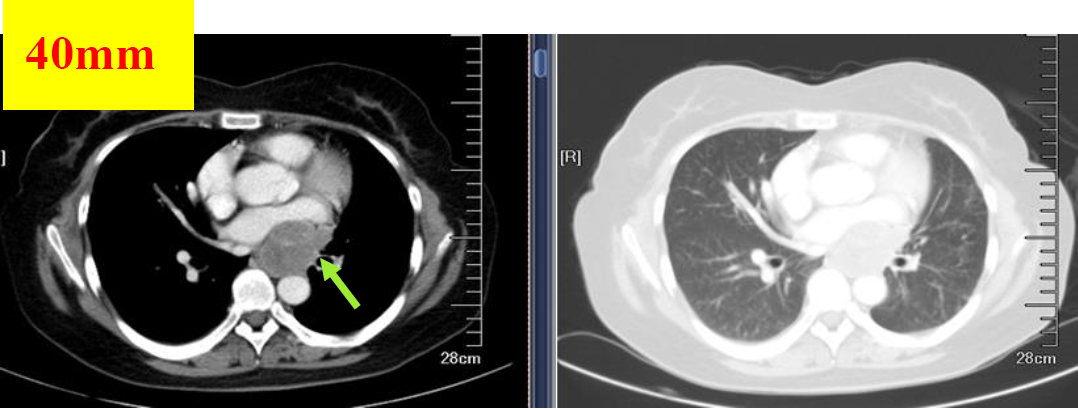

图1 2018.06.19基线检查

图2 2018.07.23影像学检查(PR)